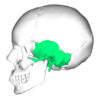

4

Q

A

temporal bone